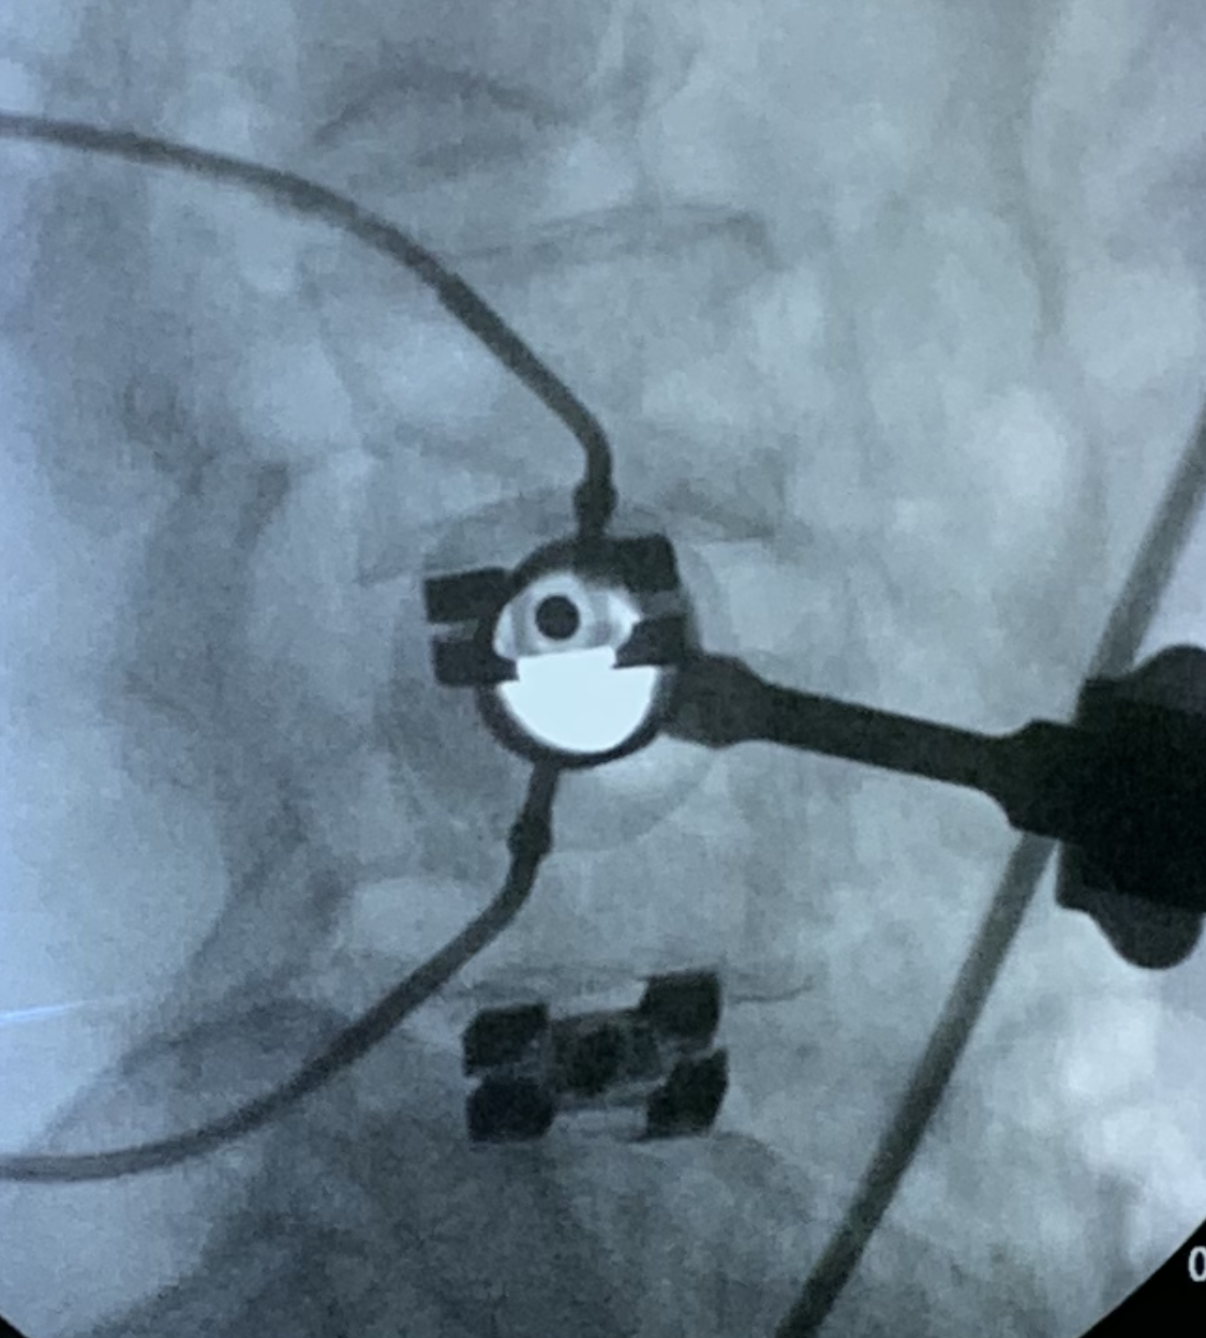

The dualX® LLIF solution is a comprehensive expandable interbody cage system for small portal access. dualX® LLIF is designed to minimize neural retraction while achieving maximum implant geometry.

The procedure is performed completely through an 18mm opening, reducing the potential psoas retraction up to 50%.

Mechanically, it's a great construct. The other major advantage dualX®Slim implant has is the post expansion fill. The expansion—which is the footprint—is biomechanically stable. I have no doubt that it's a more stable construct compared to a much smaller device that is not point loading or edge loading the end plates. And then the fact that you can really put quite a bit of graft in the disk space that you know surrounds the entire cage is—from a technical standpoint—really a major advantage in my opinion.

When you get the dualX® cage in your hand, you can see it work… You can see it in your patient doing what it's supposed to do… and you achieve the lordosis that you're supposed to achieve… and on top of that, your footprint is really large. In my mind, it is the single best cage that expands—not just in the medial-lateral footprint but also in cranial codal height and lordosis—and I think it's unmatched in the market.

While there are many expandable implants on the market, you know dualX® really has the ability to expand bidirectionally. (This) is really what makes it different, in addition to the implant's overall size…